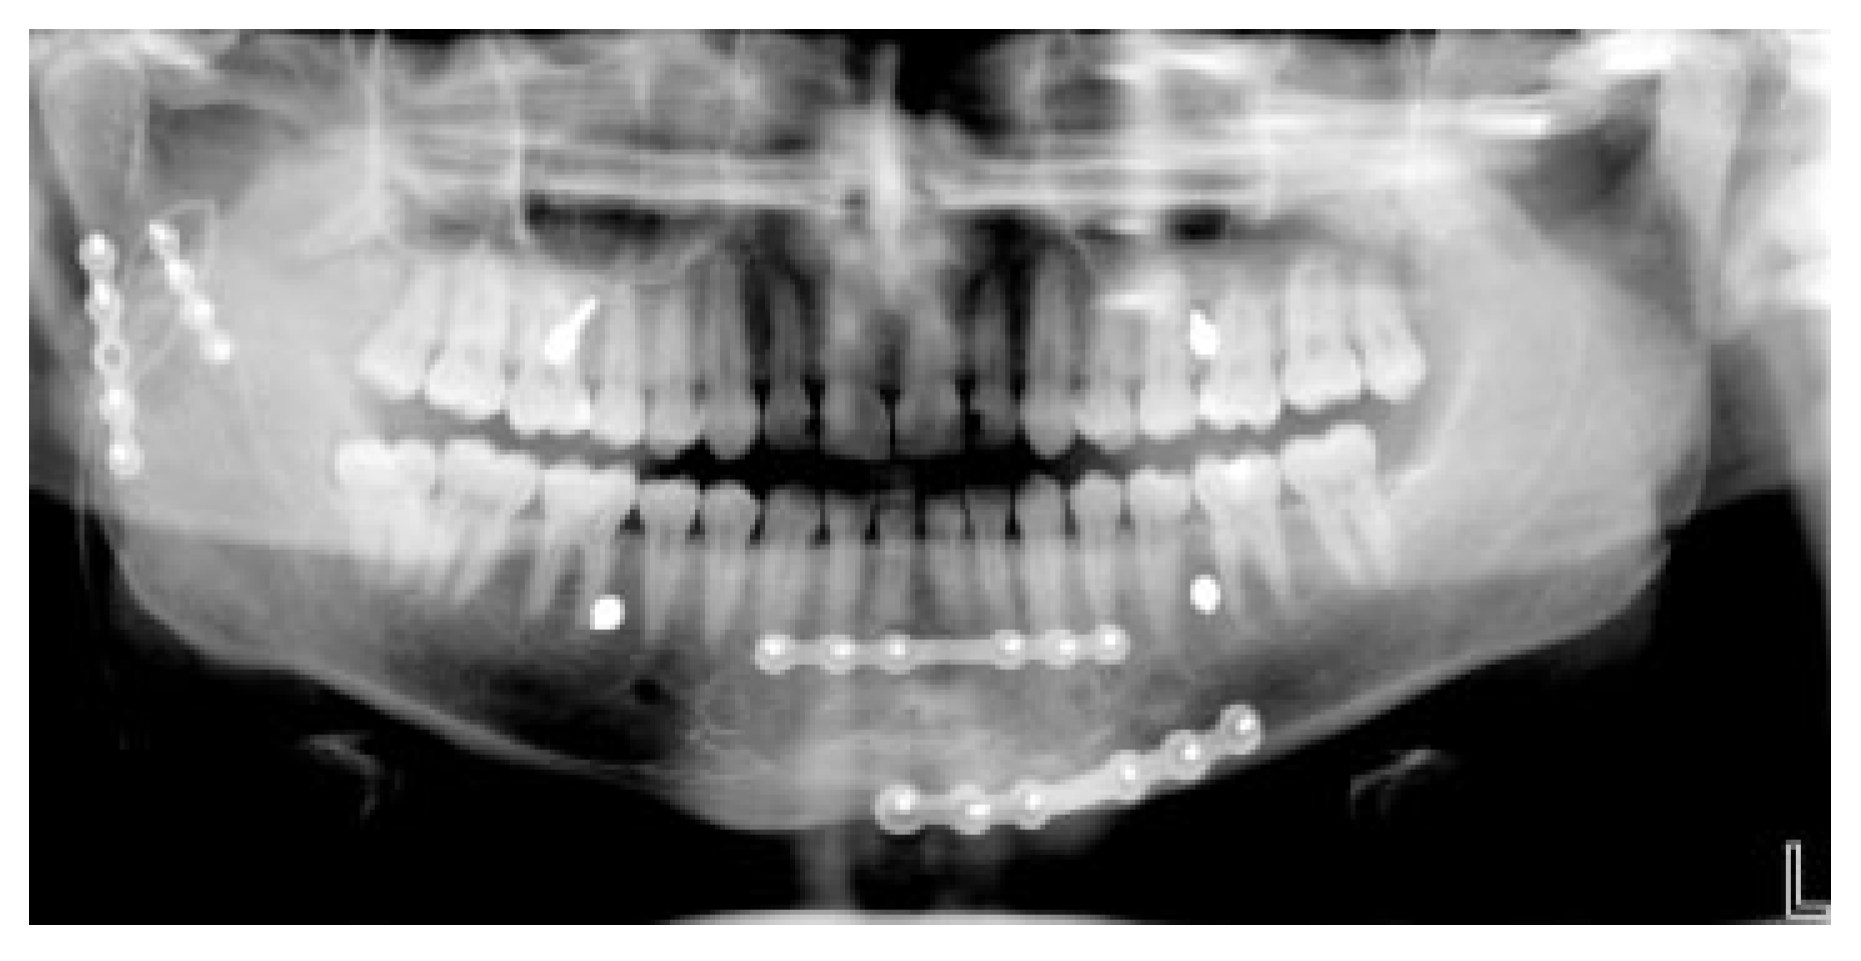

Favorable conditions include simple fractures of the fully dentate mandible and/or maxilla, since it is easy to construct a stable mandibulo-maxillary unit by the insertion of a few MMF screws and wire links (Figure 11 and Figure 12).

In comminuted and defect fractures priorities are given to anatomic reduction of the existing bone and with bridging hardware of the skeletal gaps. The applicability of MMF screws here is related to the occlusal matching of the counterparts left in the jaws. Only large uninterrupted bone portions are suitable for MMF screw insertion (Figure 17 and Figure 18).

Based on the two-dimensional projection in panoramic x-rays or dental films, dental root defects are classified according to their location, size and prognosis for survival of the injured tooth (Figure 19). Fabbroni et al. [22] distinguish minor from major contact root injuries depending on the percentage of the circumference of the hole left by an MMF screw radiographically visible adjacent or over the root formation. The threshold value to separate minor from major lesions amounts to a 50% overlap between screw hole and the dental root (Figure 20). In a retrospective radiographic study on screws used for monocortical miniplate fixation of mandibular fractures using Champy’s technique, Driemel et al. [23] characterize four types of dental root lesions. Two “central” types comprise lesions above or in the apical third of the root (including the neurovascular bundle) presumably including a pulp injury. The two “peripheral” types are not associated with pulp injuries and are located either in the radicular dentin, cement, or peridontal space

Both studies found that the occurence of major radiographic lesions was not reliable in predicting clinical sequelae in terms of vitality testing or the necessity for endodontic treatment, apicetomies or tooth removal. This was explained by the radiographic assessment technique (periapical dental films or panoramic radio-graphs), which cannot reveal the actual depth of penetration or the involvement of the dental pulp chamber (Figure 21).